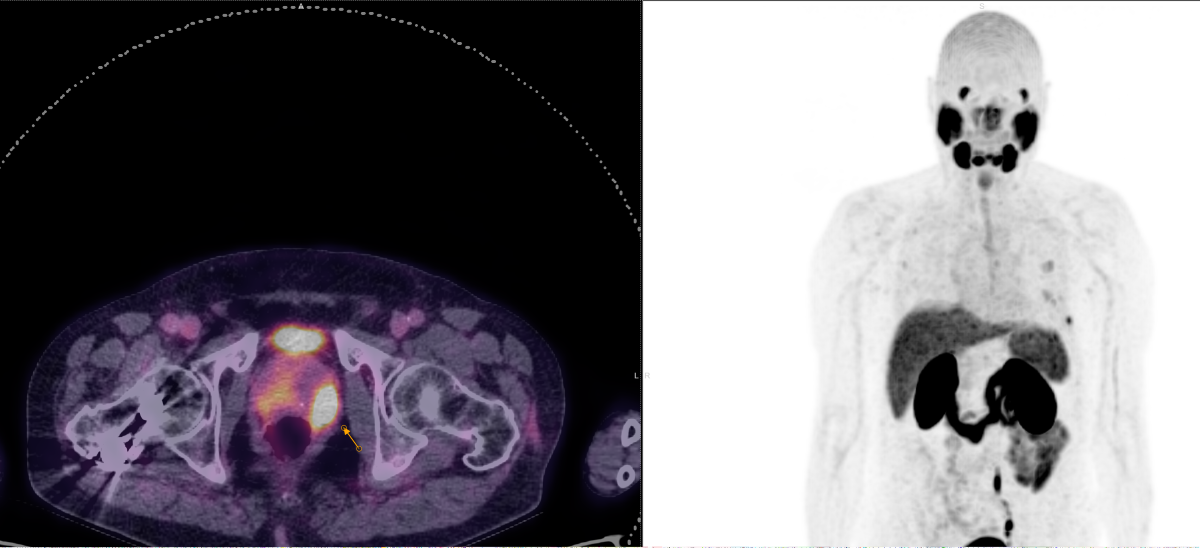

Με τη χρήση ειδικού λογισμικού Τεχνητής Νοημοσύνης (MIM – Lesion ID) πραγματοποιείται αυτόματος υπολογισμός της έκτασης και του όγκου των θέσεων ενεργού νόσου. Ξεπερνώντας τις δυνατότητες του ανθρώπινου οφθαλμού υπολογίζεται το συνολικό φορτίο νόσου πριν και μετά την θεραπεία επιτρέποντας ακριβέστερο χειρισμό του ασθενούς από τον θεράποντα ιατρό.

ΠΟΣΟΤΙΚΗ ΕΚΤΙΜΗΣΗ – ΜΕΤΡΗΣΗ ΟΓΚΟΥ ΝΟΣΟΥ

PSMA‑θετικός καρκίνος προστάτη

Νευροενδοκρινικοί όγκοι (SSTR)